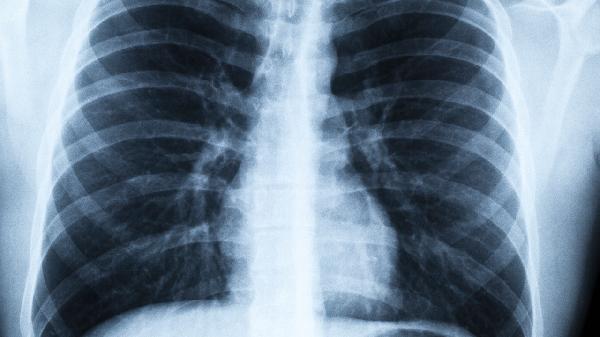

1、低剂量CT比胸片更靠谱

能发现小至2mm的微小结节,辐射量仅相当于乘坐2小时飞机。建议高危人群每年检查一次。